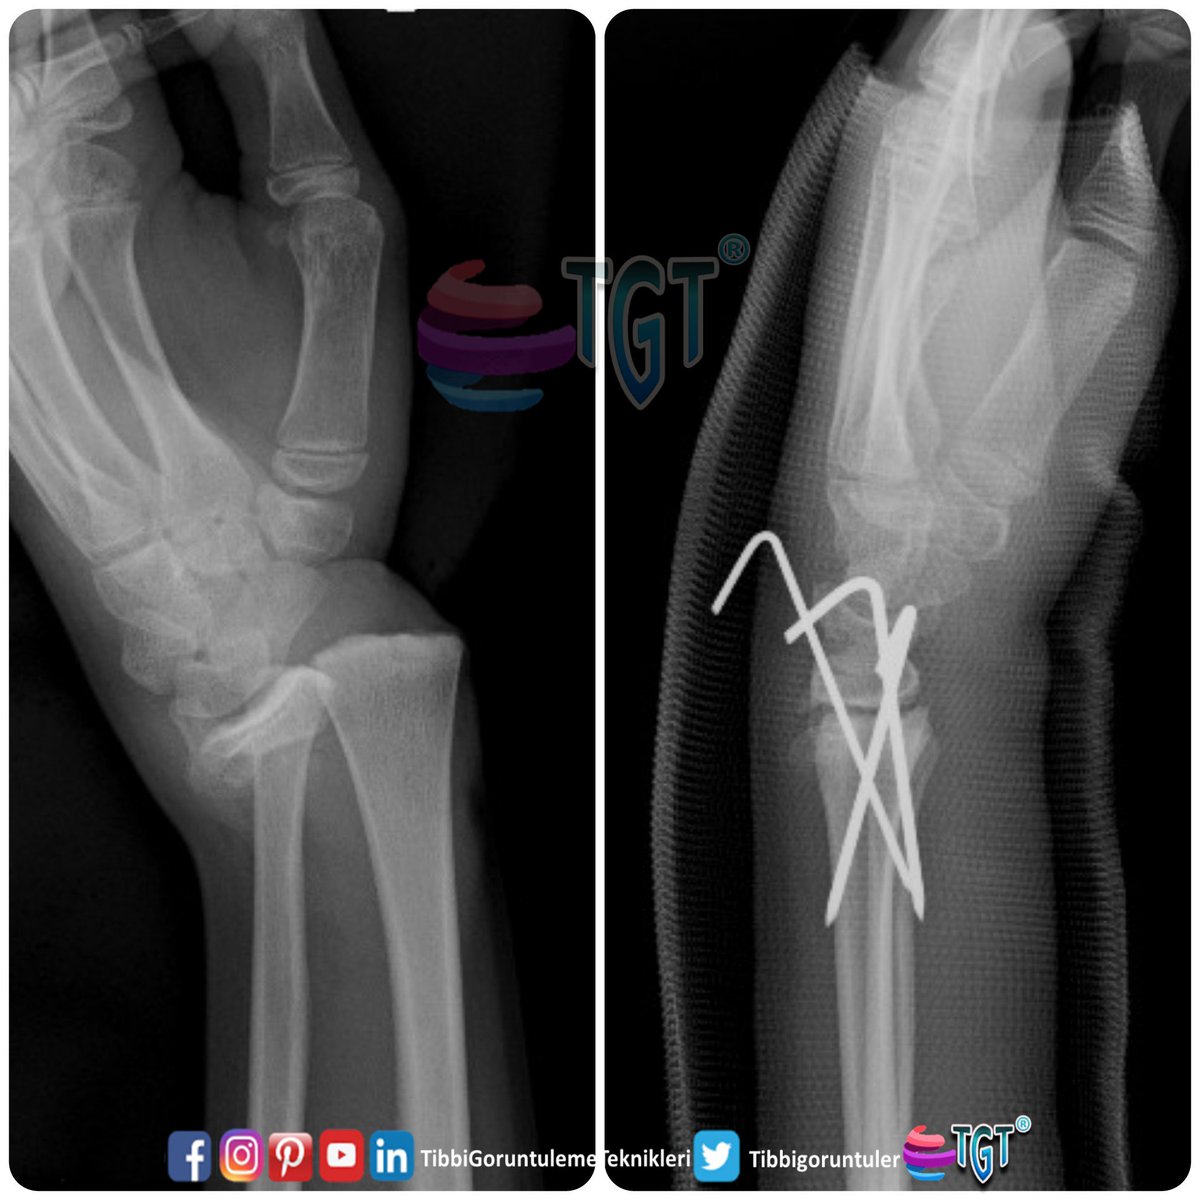

Tgt On Twitter El Bilegi Kirigi Ameliyati Oncesi Sonrasi Wrist Fracture Surgery Before After Wristfracture Tibbigoruntulemeteknikleri Https T Co Vs1g6peevo